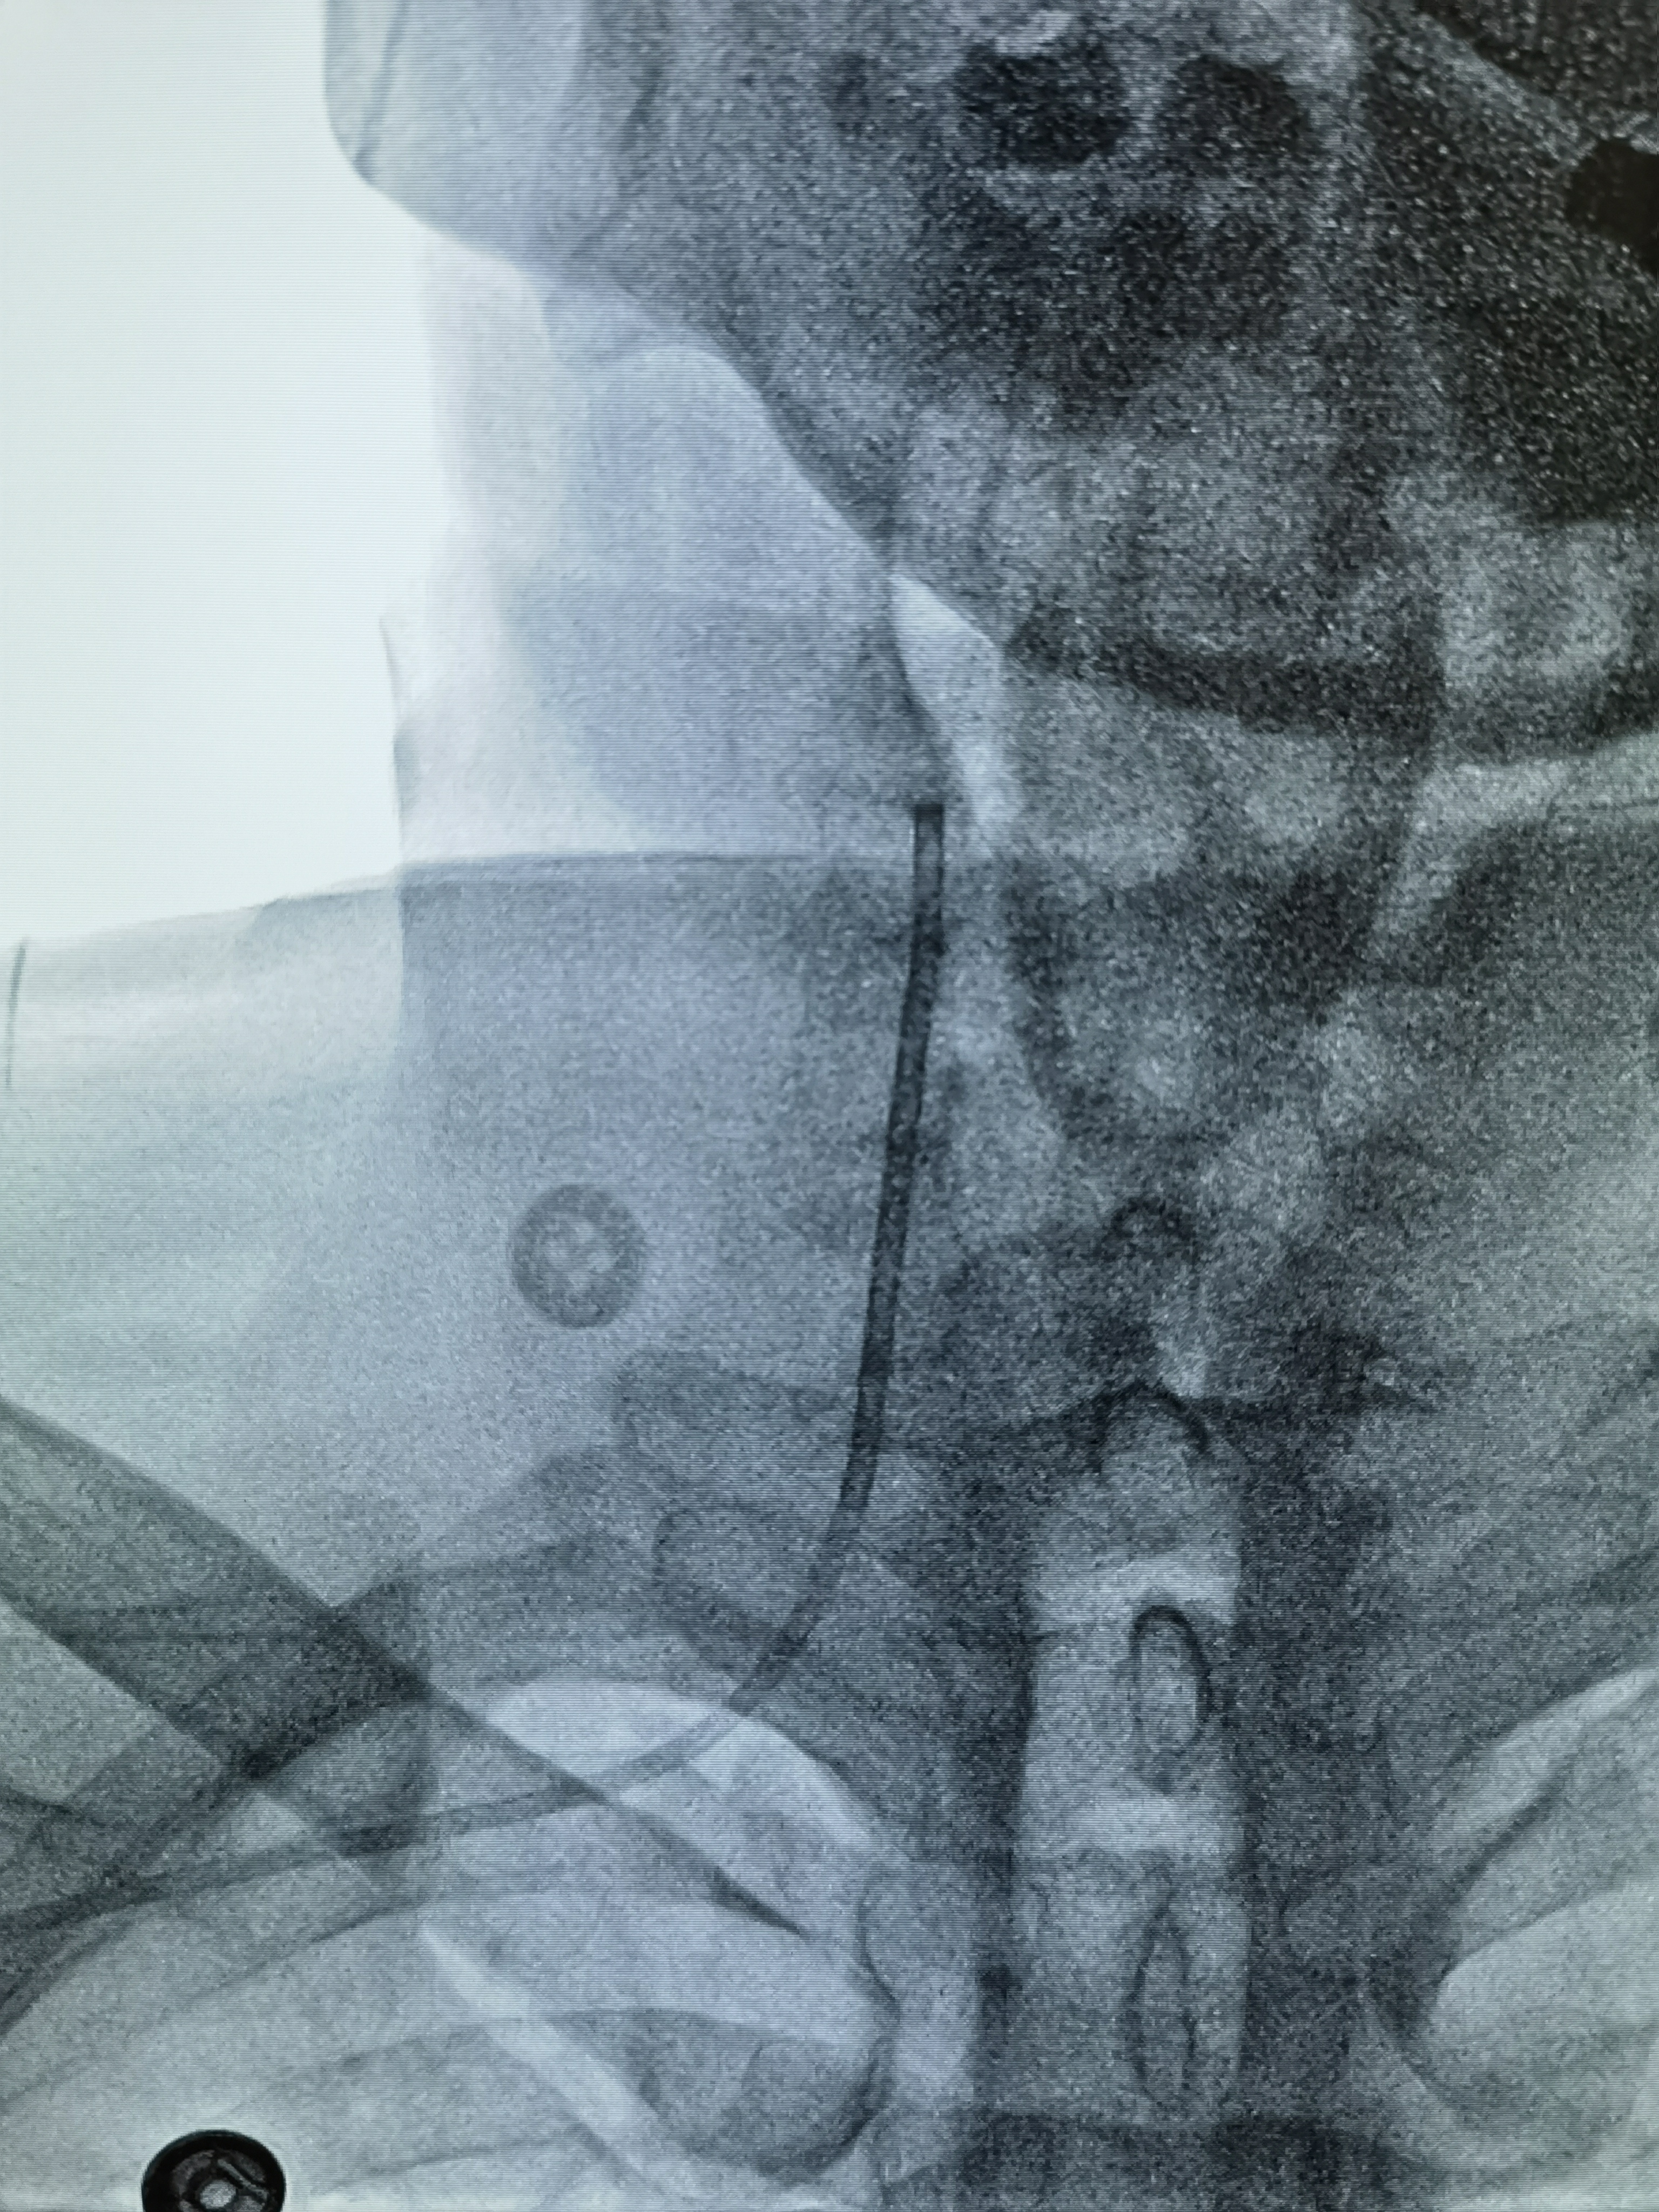

右桡动脉入路,6FMPD指引导管头端置于V2段,内衬5F禾木117中间导管头端置于颅内段!

Gateway2.5*15压力打至8atm

释放3.5*17Lvis支架

蒙片看支架打开贴壁良好